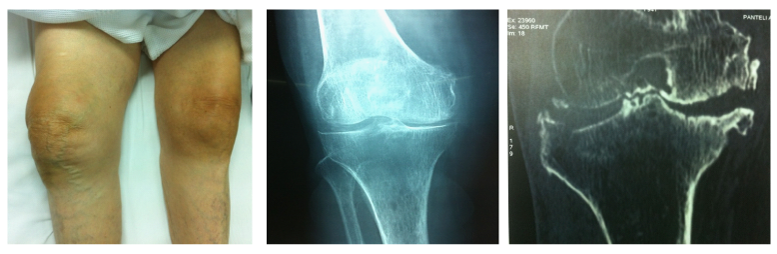

A 91-year-old woman sustained a right lateral tibial plateau depression fracture due to minor trauma (fall while walking). At presentation, the patient had significant knee effusion and was unable to weight bear on the injured leg. Nevertheless, her initial X-rays did not reveal anything more than severe arthritis of her knee. The subsequent CT scan - ordered because of high clinical suspicion - revealed a depression fracture of her lateral tibial plateau without cleavage (Figure 1). Apart from the tibial fracture, the patient had significant comorbidities including six fractured ribs, haemothorax and mild pneumothorax resulting from the same injury as well as cardiac arrhythmia (treated with a pacemaker), severe osteoporosis and adhesive intestinal obstruction. In order to achieve early mobilization of the patient and minimal knee stiffness, surgical treatment was chosen using a minimally invasive technique: Reduction of the depressed tibial plateau using balloon tibioplasty and stabilization of the fracture with hydroxyapatite cement and cannulated screws.

Figure 1 Clinical presentation, X-ray and CT scan.